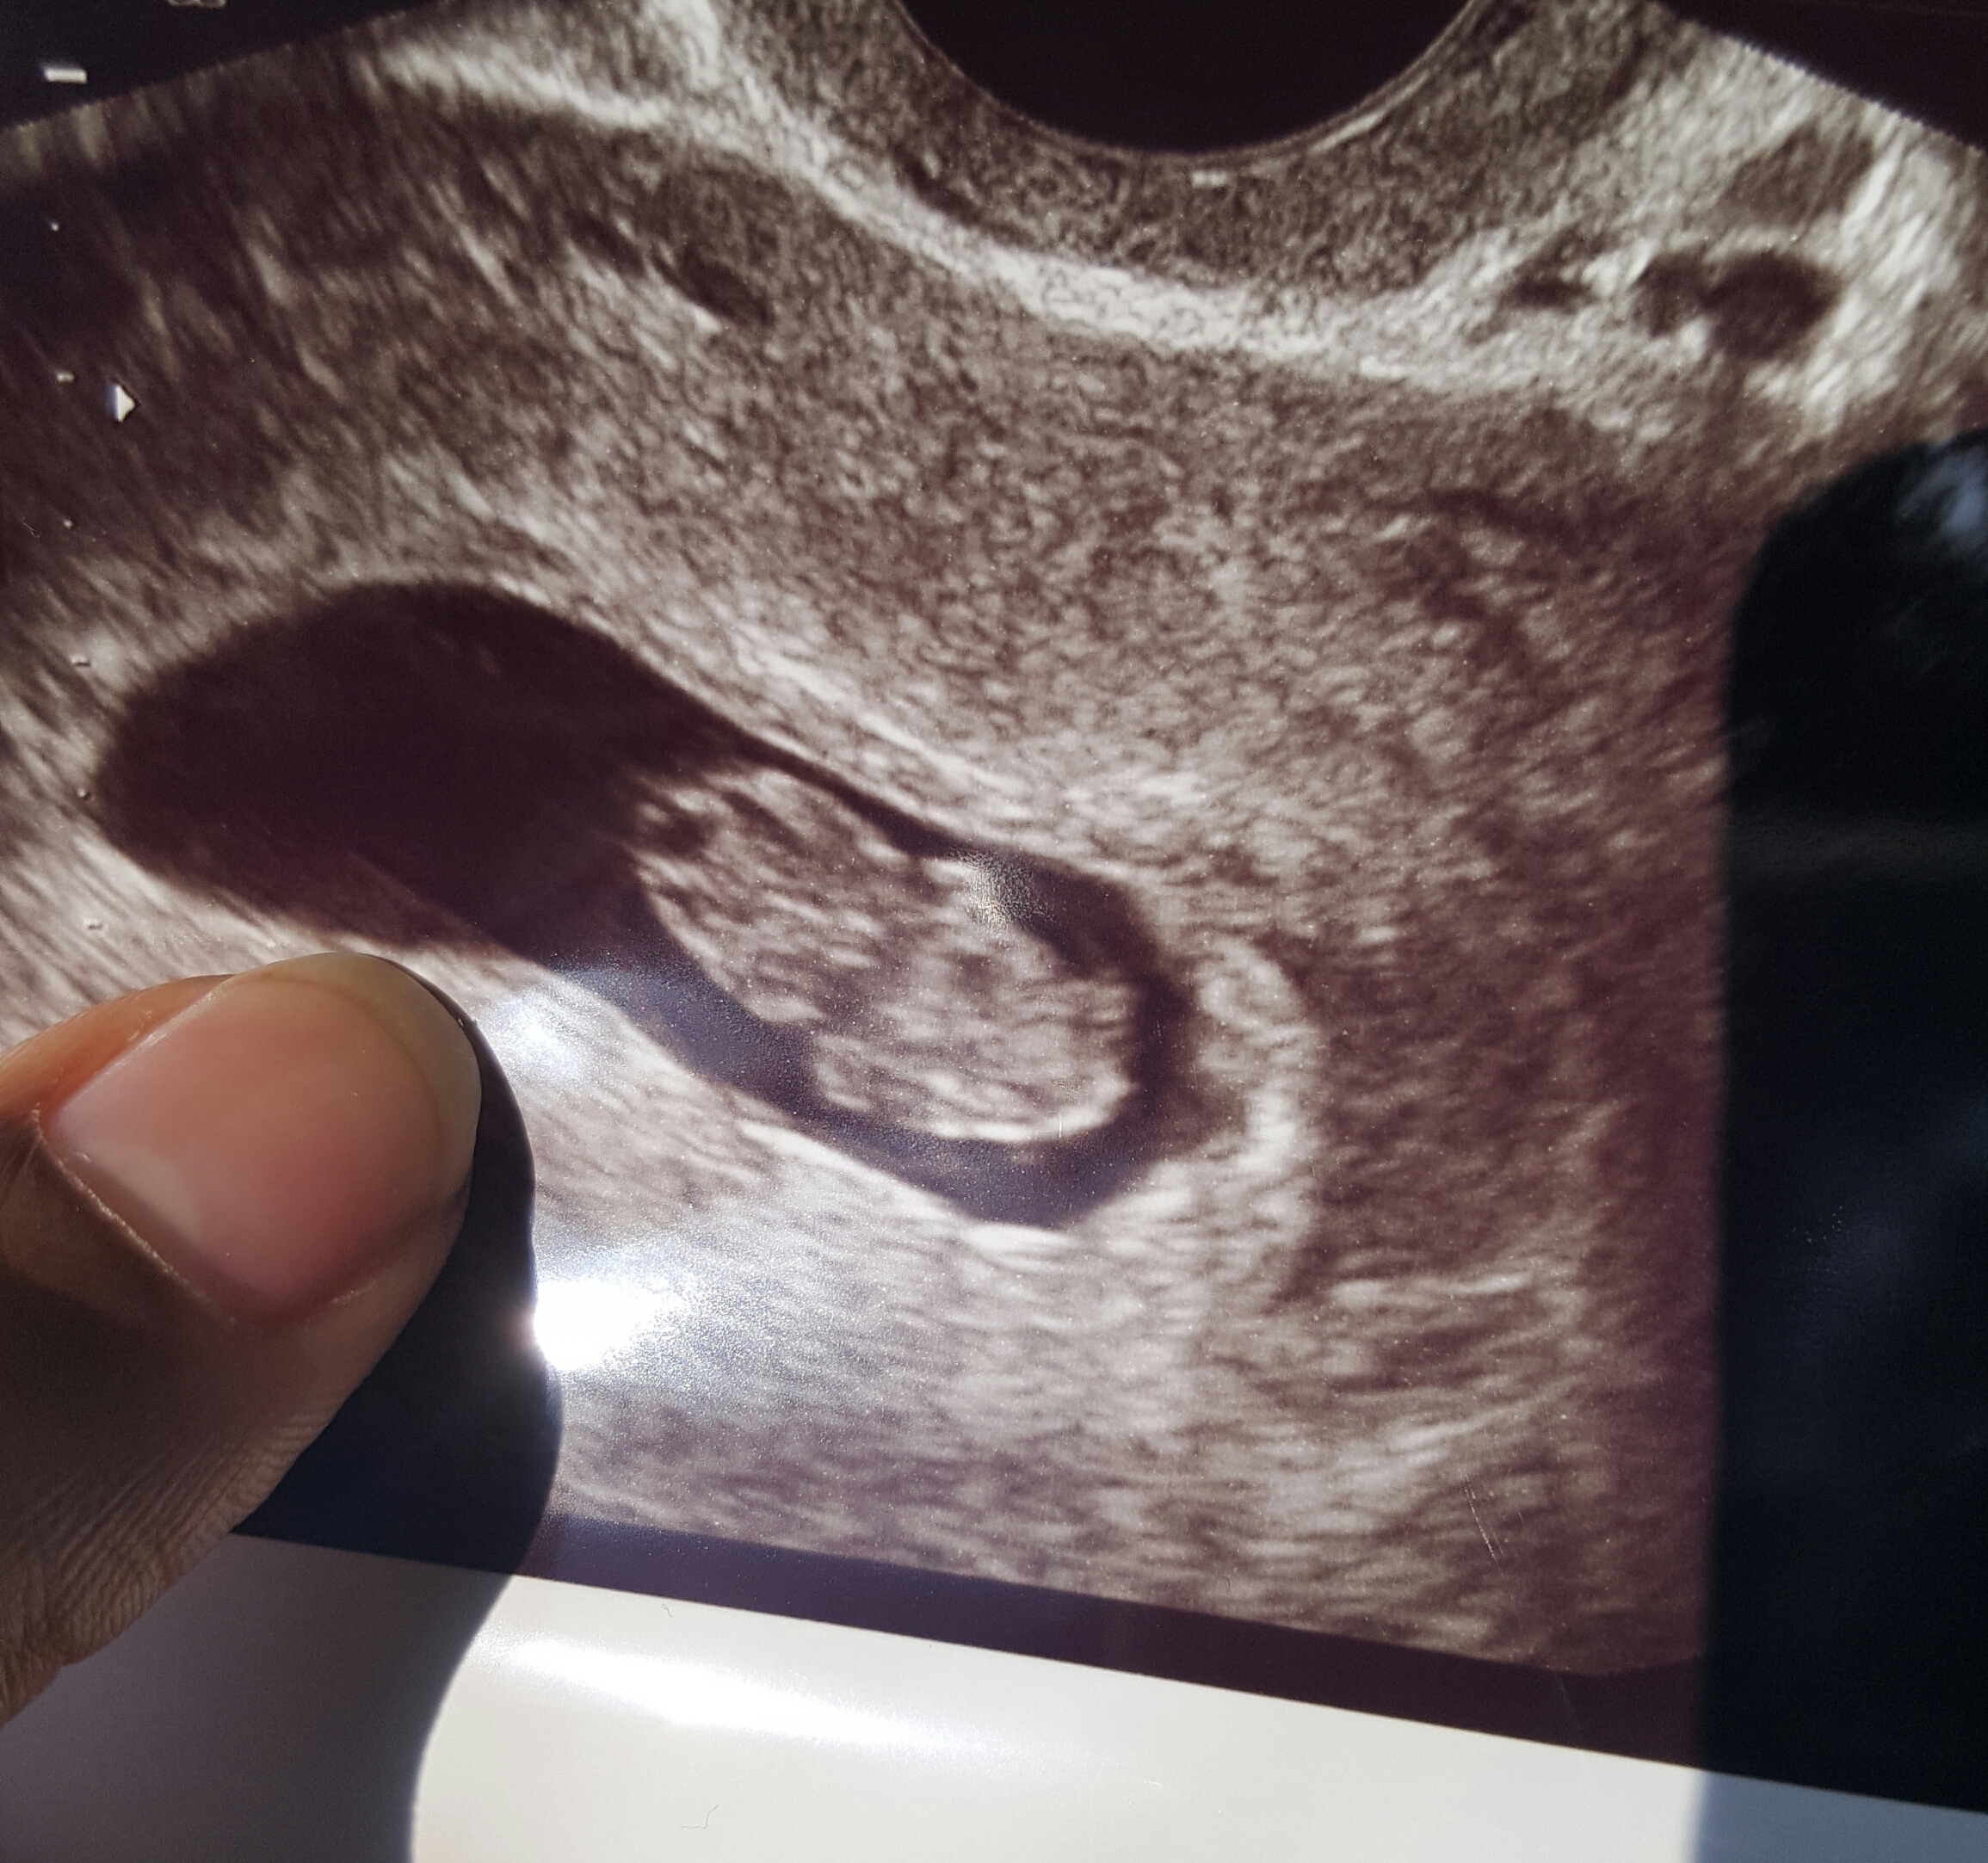

• I still can't get over the difference a few days makes. Up there ^^^ I posted 6 weeks and 8 weeks (thursday) and this was today at 8.5 weeks. Look at the little arms!!! And already 2 inches long???

I still can't get over the difference a few days makes. Up there ^^^ I posted 6 weeks and 8 weeks (thursday) and this was today at 8.5 weeks. Look at the little arms!!! And already 2 inches long???

My first three were internal (6 weeks, 8 weeks, 8.5 weeks). They are much much more clear than my external I had this week (11 weeks).